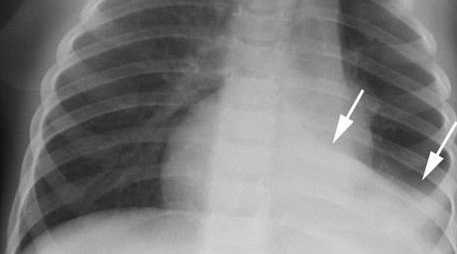

Диагноз подтверждается рентгенологически. Рассеянный ателектаз легких у новорожденных на рентгеновском снимке представлен множественными участками затемнения небольших размеров. Характерно преимущественно паравертебральное расположение безвоздушных областей. Сегментарный ателектаз легких у новорожденных выглядит, как обширный участок затемнения. При высокой разрешающей способности аппаратуры можно заметить сморщенный участок легочной ткани возле корня легкого. Часто отмечается смещение сердца в пораженную сторону и более высокое стояние диафрагмы со стороны ателектаза. Для подтверждения диагноза, особенно при подозрении на обструкцию дыхательных путей, показана бронхоскопия.

Основу инструментальной диагностики ателектаза легкого составляют рентгенологические исследования, прежде всего, рентгенография легких в прямой и боковой проекциях. Для рентгенологической картины ателектаза характерно гомогенное затенение соответствующего легочного поля, смещение средостения в сторону ателектаза (при коллапсе легкого - в здоровую сторону), высокое положение купола диафрагмы на пораженной стороне, повышенная воздушность противоположного легкого. При рентгеноскопии легких на вдохе органы средостения смещаются в сторону спавшегося легкого, на выдохе и при кашле - в сторону здорового легкого. В сомнительных случаях данные рентгенографии уточняются с помощью КТ легких.

Еще одна суб-разновидность этого типа — так называемый дисковидный ателектаз, неполное расширение долей легкого с образованием на рентгене картины в виде поперечных полос.

![дисковидный-ателектаз-на-рентгене]()

При проведении рентгенологического исследования на рентгенограммах определяется тень, имеющая четкие вогнутые границы. При проведении рентгеноскопии у пациентов с ателектазом легкого можно выявить симптом Якобсона-Гельцнехта (толчкообразные смещения тени средостения, направленные в сторону поражения).

Проводится диагностика при помощи рентгенологического исследования в разных проекциях. На снимки видно затемнение травмированного участка легкого, диафрагма занимает повышенное положение по отношению к пораженной стороне. Часто снимки не дают поставить точный диагноз, и тогда диагностика проходит при помощи другого метода — компьютерная томография легких.